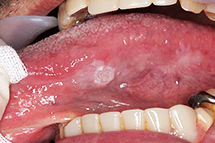

歯石が歯茎に刺激を与えると、歯茎が赤く腫れたり出血したりする歯肉炎を引き起こします。この状態が悪化すると、歯周病に進行し、歯を支える骨が徐々に溶けていきます。最終的には、歯を失う原因となることもあります。歯周病を予防するためには、歯石を早期に取り除くことが重要です。